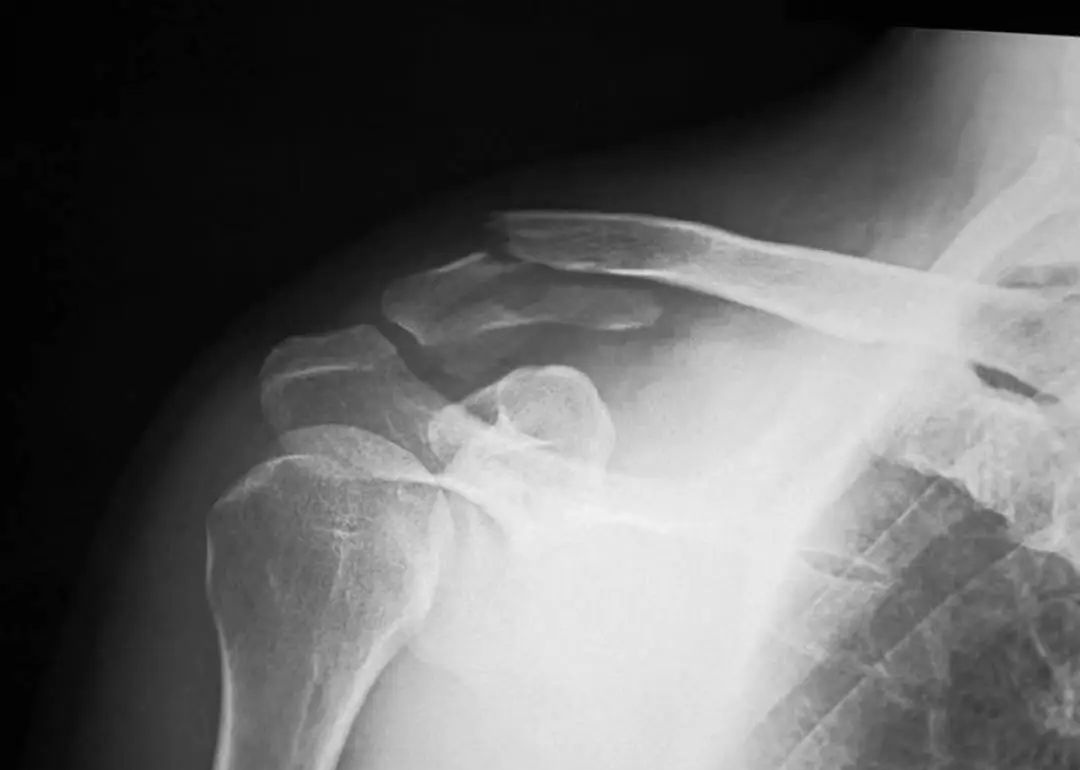

手术治疗方法包括1~枚克氏针、螺纹针、螺丝钉经肩峰进行固定、喙锁螺丝钉固定、喙突移位、张力带以及接骨板等。目前多采用锁骨钩接骨板进行复位后的固定,该治疗方法具有固定物放置容易、可较为准确的维持复位、不破坏肩锁关节、内固定物相对稳定等优点,不会像传统的克氏针一样向周围组织发生滑移。但该治疗方式易导致患者在术后功能锻炼时产生的应力沿肩锁关节向锁骨传导,在接骨板的内侧部位造成应力集中,并出现应力骨折。

锁骨板有哪些【每周科普】锁骨骨折分中段、外段、内段,治疗方式也有差异_https://www.jmylbn.com_新闻资讯_第13张

锁骨钩接骨板内固定术后应力骨折